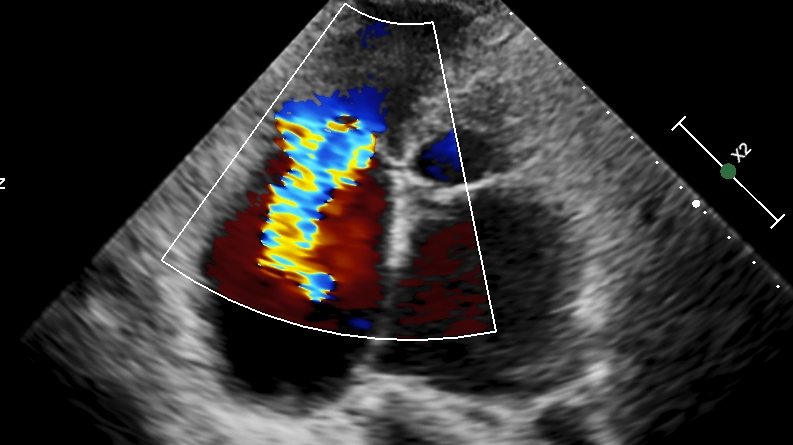

进一步三维经食道超声提示三尖瓣瓣叶活动可,无明显脱垂,隔瓣较小,反流束来源于前瓣及隔瓣对合缘,对合缘明显关闭间隙,反流束同时向后隔交接延申(视频1)。

视频1: 3D TEE彩色多普勒提示三尖瓣重度反流,反流口位于隔瓣及前瓣交接,向后瓣及隔瓣交界延申。